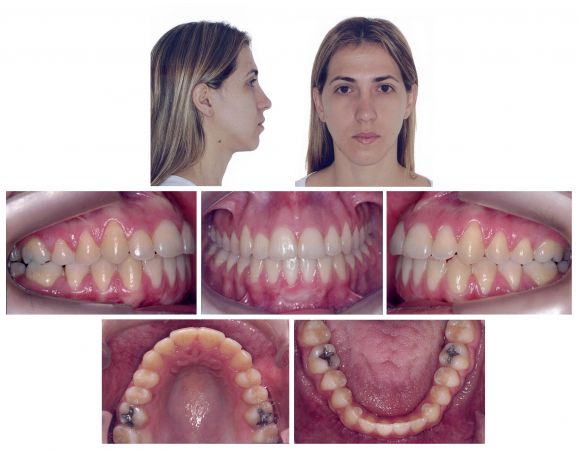

Pós-contenção

Finais